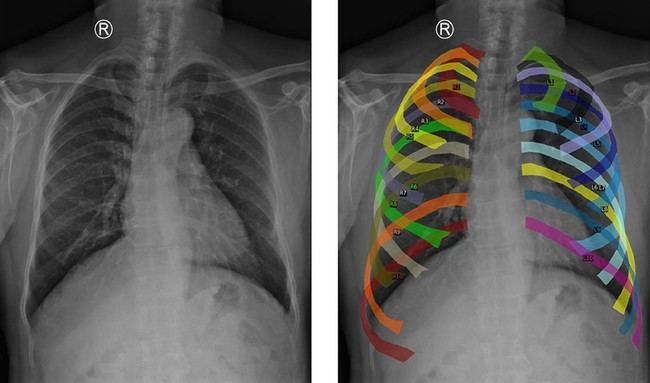

Para optimizar el entrenamiento del modelo, se han utilizado datos provenientes de varios centros hospitalarios junto con una técnica conocida como aumento de datos. Esta estrategia permite segmentar costillas y alinear puntos clave del tórax para generar imágenes homogéneas desde una perspectiva anatómica. Así se asegura que el sistema sea robusto ante variaciones en las radiografías provenientes de distintos hospitales o equipos.